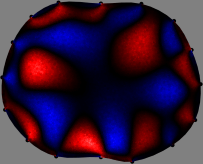

Figs. 3 and 4 compare the performance of the proposed FER method in (20) with the standard regularized least-squares method ((19) when is the identity matrix). The regularization parameter of the standard method was heuristically chosen for its best performance, and the parameter of the FER method was set to be one of three different values . The injection current was 1 mA at 100 kHz, and the frame rate was 9 frames per second. The reference frame at was obtained from the maximum expiration state. The measured data, , represent the voltage differences between each time and . The blue regions, which denote where conductivity decreased by inhaled air, increased during inspiration and decreased during expiration. The FER method with was clearly more robust than the standard method that produced more artifacts originated from the inversion process.

| Standard | |

||||||||||

| FER () | |